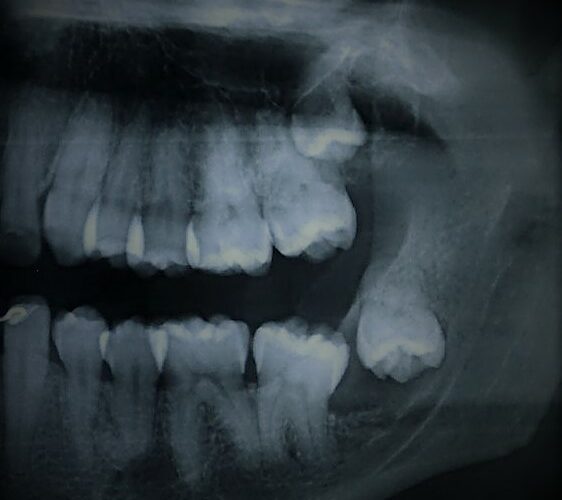

Muitos pacientes apresentam dentes que não irromperam (nasceram) total ou parcialmente, necessitando de procedimentos para tratamento. O procedimento mais comum é a exodontia (remoção) dos sisos (dentes do juízo). Mas existem outros procedimentos que podem ser indicados, como exemplo, o tracionamento de caninos inclusos.

É importante deixar claro que nem todos os sisos precisam ser removidos. As indicações mais comuns são devido a infecções (pericoronarites), cáries, doença periodontal, cistos associados e mordedura da mucosa jugal (bochecha).

Todas essas indicações podem causar desconforto. A definição se o siso está em boa posição e não precisa ser removido deve ser realizada por um cirurgião dentista. Caso indicado a remoção de um ou mais sisos, preferencialmente indica-se realizar na fase final da adolescência ou início da fase adulta, pois suas raízes ainda não estarão totalmente formadas. Mas, não existem limites de idade para remoção de dentes inclusos, quando o procedimento for necessário.